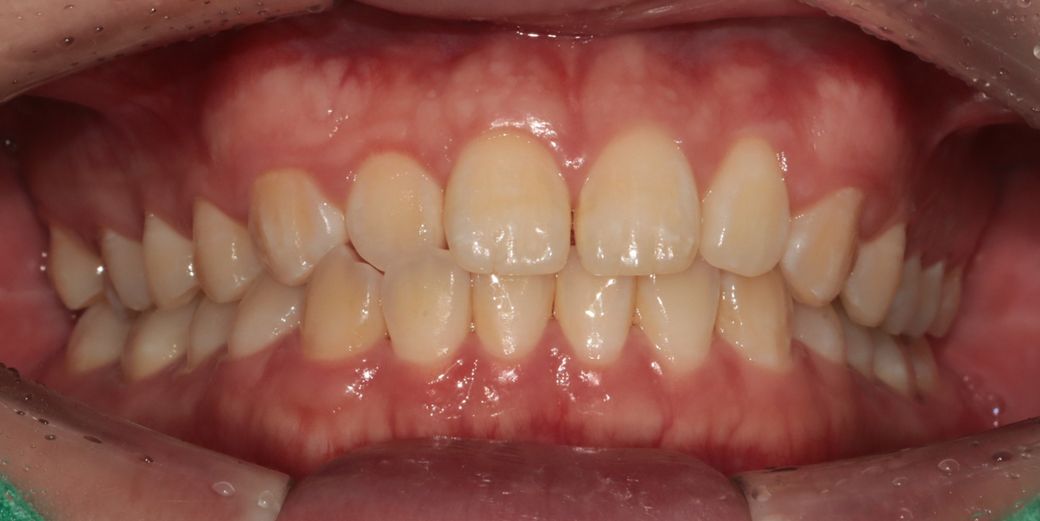

옆모습이 하악턱과 입이 튀어나와보여 컴플렉스 인 남성입니다 다른사람이 보기에는 어떨지는 모르겠습니다

그런데 미용적으로 개선하고싶으나 양악하기에는 부작용도 무섭고 수술도 무서워요 죽을수도 있다고 들어서요...그래서 고민하는게

1번 양악-가장드라마틱하게 턱도줄이고 입툭튀도 줄일수있을것같긴해요

2번 -발치교정하기에 치열이 아까운것같아 사랑니쪽으로 전체이동 비발치교정 하기-이러면 입툭튀 조금은들어간다고 들었어요 대신 입이들어가서 턱이 조금나와볼일수있다는데 치아 들어가도 2~3mm라 별차이 없을수도 있다고들어서...맞는지는 모르겠습니다

(현재 사랑니4개 없는상태입니다)

전문의가 평가하기에 1,2,3번중 어느게 맞을까요?

지난번에도 설명드렷지만 개인적으로는 아무것도 안하셔도될것같습니다. 크게 문제가 있어보이진 않아요. 하지만 작성자님께서 계속 글을 적으시는건 컴플렉스가 있어서 그런거 같으니 만약 치료를 원하신다면 양악케이스는 아닌것 같고 교정을 통해서 심미적인 부분을 해결하시는게 좋을것같습니다

개인적으로는 2번이 적당한것 같습니다.

1번은 위험부담이 크고, 3번은 미련이 남을것 같기 때문 입니다.